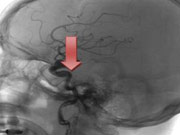

根据数据分析显示,在燕达医院神经外科所收治的脑血管疾病患者在所有疾病类型患者中属(zui)高,其严重性不言而喻。近期,燕达医院神经外一科就收治了一位备受脑血管病困扰的外地老年患者高大爷(化名)。